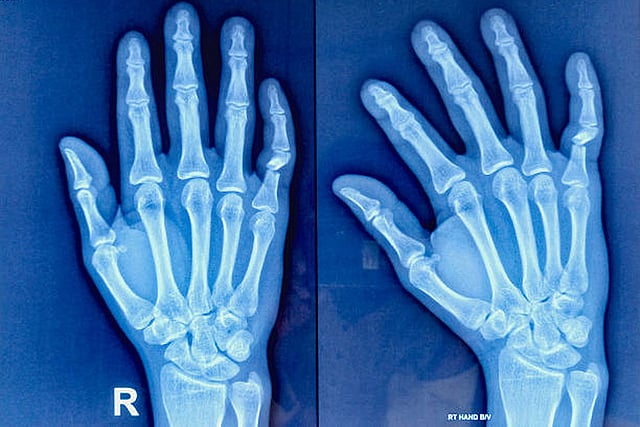

सोरायसिस से पीड़ित लगभग 20 से 30 प्रतिशत लोगों में आगे चलकर सोरायटिक आर्थराइटिस विकसित हो सकता है। फोटो साभार: आईस्टॉक

लेकिन लगभग 20 से 30 प्रतिशत लोगों में, जिनको सोरायसिस होता है, आगे चलकर जोड़ों में दर्द और सूजन भी शुरू हो जाती है। इस स्थिति को सोरायटिक आर्थराइटिस कहा जाता है। यदि इसका इलाज समय पर न हो, तो यह हड्डियों और जोड़ों को स्थायी नुकसान पहुंचा सकती है।